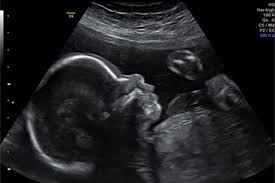

L’échographie est un examen complémentaire, accessible et fiable dans la prise en charge de diverses pathologies. De plus, elle demeure aussi un examen très prisé pour une étude minutieuse de la grossesse de ses débuts jusqu’à ses termes. En effet l’échographie fœtale est plus que recommandée dans le suivi du développement d’une grossesse. Elle a énormément soulagé les gynécologues et les sages-femmes sur le plan gynéco-obstétrique en leur permettant de répondre à plusieurs questions (vitalité, évolution de la grossesse, présentation, etc.) à propos du fœtus ou de l’utérus et de ses annexes (myome, kyste, etc.), et de diagnostiquer très tôt les malformations fœtales et utérines. Il est inutile, ici, d’épiloguer sur l’intérêt de ce moyen d’investigation dans la surveillance fœtale.

- Échographie obstétricale

L’échographie permet aussi de déceler chez la femme enceinte le fœtus en présentation par le siège, ce qui est incontestablement un fœtus à risque. Une appréciation précise des risques de cette présentation permet une prise en charge adéquate de la femme et de l’enfant.

- Présentation anormales

Dans les pays en voie de développement comme le Niger, la présentation du siège pose un problème de diagnostic, de surveillance et de prise en charge adaptée d’où l’intérêt pour les femmes enceintes de pouvoir faire l’échographie au cours de leur grossesse, au moins trois fois comme conseillé par l’OMS, c’est-à-dire à chaque trimestre de la grossesse.